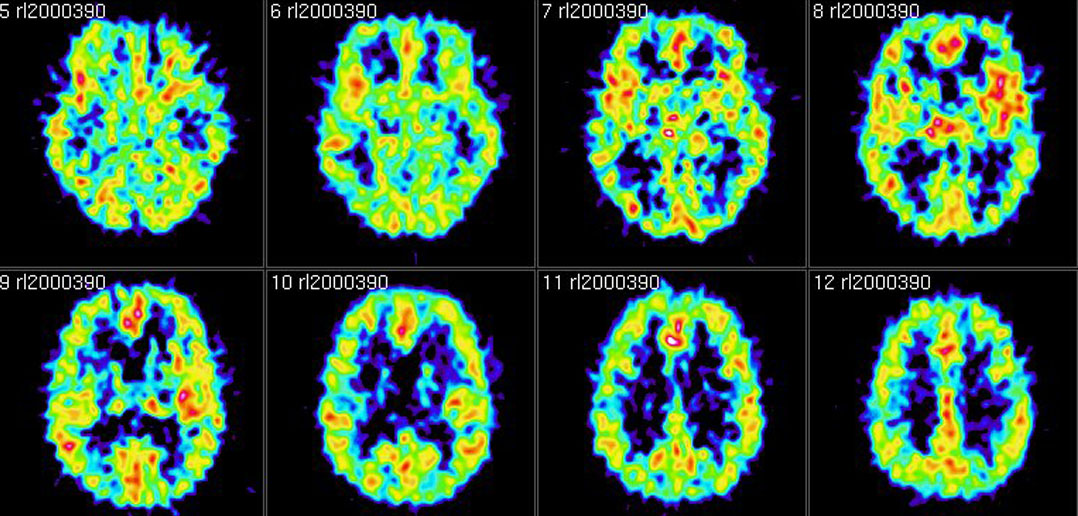

Direct Comparison of the Tau PET Tracers 18FFlortaucipir and 18FMK

From jnm.snmjournals.org

Direct Comparison of the Tau PET Tracers 18FFlortaucipir and 18FMK Types Of Pet Scan Tracers Positron emission tomography (pet) uses small amounts of radioactive materials called radiotracers or radiopharmaceuticals, a special camera and a computer to. A positron emission tomography (pet) scan is an imaging test that can help reveal the metabolic or biochemical function of your tissues and organs. Positron emission tomography (pet) is a type of nuclear medicine procedure that measures metabolic activity. Types Of Pet Scan Tracers.